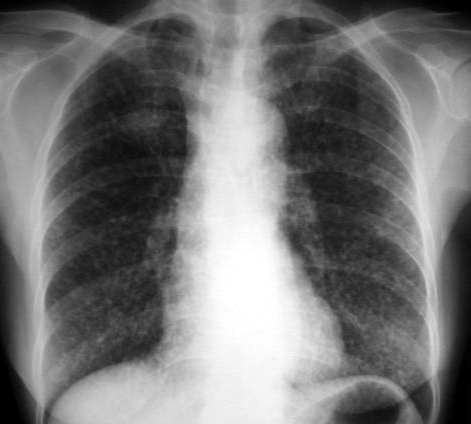

黄某,女,66岁,胸闷、咳嗽1个月,近日体重减轻。请讨论

胸廓饱满,双肺透亮度高,未见明显实变阴影,纹理稀疏,余未见明显异常。考虑肺气肿。

两肺见弥漫分布的小粟粒状影,考虑:1、血播tb;2、肺泡细泡癌;3、肺内转移病变。

右肺上叶斑块状影,双肺弥漫分布多发小结节影,以双下肺叶为著。

考虑:1、右侧肺癌并双肺内血行转移。

2、肺泡细胞癌。

3、不除外血行播散型肺结核,建议结合临床查痰或做结核菌素实验。